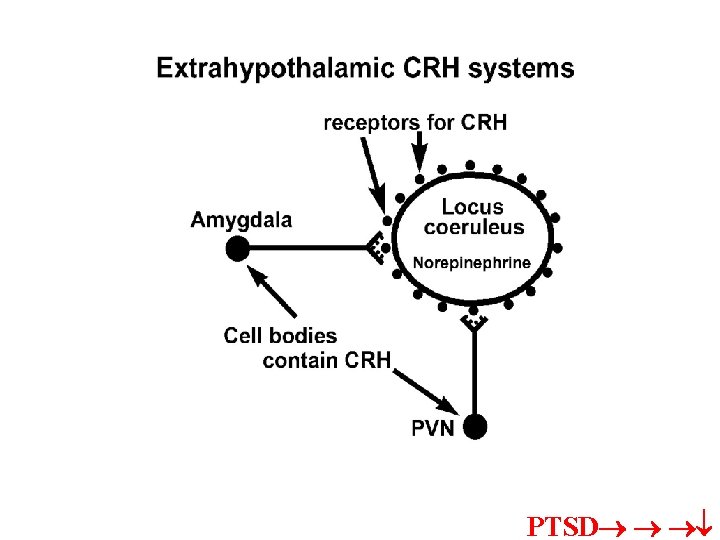

SENSORY inputs to LATERAL NUCLEUS; then relayed to basal, and accessory basal to reach: CENTRAL NUC =OUTPUT CRH receptors on cells and uses CRH as transmitter to LC adrenal medulla via pregang. sym. CRH ventricles

CRH into severe ventricles=turn on fear response and hypervigilance; CRH antagonists central nuc=reduction in the occurrence of above reactions • Target CRHCRH Amyg. conn